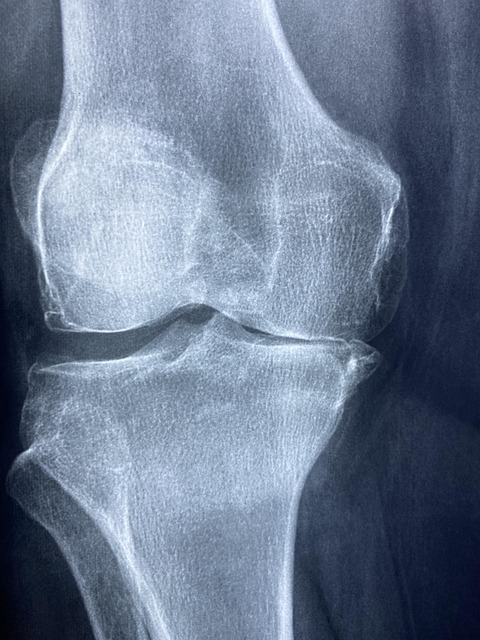

다이어트를 결심하는 많은 사람들이 관절 통증, 특히 무릎이나 고관절, 발목 관절의 통증 때문에 운동을 포기하거나 망설이는 경우가 많습니다. 특히 40대 이후 중장년층이나 퇴행성 관절염을 경험하고 있는 이들에게는 무리한 유산소 운동이나 체중 부하가 큰 근력운동은 오히려 관절 손상이나 통증 악화를 초래할 수 있어 주의가 필요합니다. 하지만 체중 감량은 관절 건강에 매우 중요합니다. 과체중이나 복부비만은 관절에 가해지는 하중을 증가시켜 연골의 마모 속도를 앞당기고, 관절염을 악화시키는 주요 원인이 됩니다. 실제로 체중 1kg이 증가할 때마다 무릎에 가해지는 하중은 3~4kg 증가하며, 이는 일상생활 중 관절 통증을 더욱 심화시킬 수 있습니다. 이러한 상황에서는 고강도 운동 대신, 관절에 부담을 최소화하면서도 에너지 소비가 가능하도록 설계된 저강도 유산소 운동을 실천하는 것이 관건입니다. 관절을 보호하면서 체중을 효과적으로 감량할 수 있는 방법은 분명히 존재합니다.